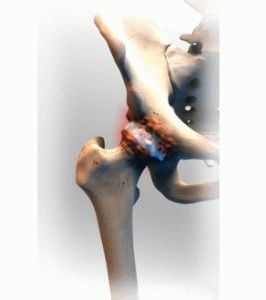

artrită șold

complicație supurativă artritei șold este un abces, care rezultă din acumularea maselor purulente. A format o fistula. Patologie se dezvolta de multe ori, atunci când tuberculoza. In functie de cauza, prezența unui tratament adecvat pentru prognosticul bolii depinde de curenți. În condiții nefavorabile, artrita reactivă se dezvoltă într-un supurau.

Un copil bolnav trimis la raze X. Puteți înlocui studiul ultrasonografie, în funcție de consultanță de specialitate, vârsta copilului. Va trebui să verifice plămâni. fluoroscopia convențional adecvat pentru a detecta prezența patologiei. Poate că experții consideră că este necesar pentru a face testul Mantoux. Ar trebui să treacă o examinare cuprinzătoare, va fi inițial chestionarea orală a pacientului, un studiu al zonei afectate.

Totul depinde de modul în care articulațiilor uimit ca simptome pronunțate. Un puternic grad de deteriorare va provoca schimbări serioase încalcă activitatea motorie a copilului din cauza durerii. Dacă timpul nu caută ajutor de la un medic, procesul merge într-o formă cronică. În acest caz, pentru a vindeca boala nu este pe deplin succes, țesutul conjunctiv va avea de suferit ca urmare a inflamatiei.